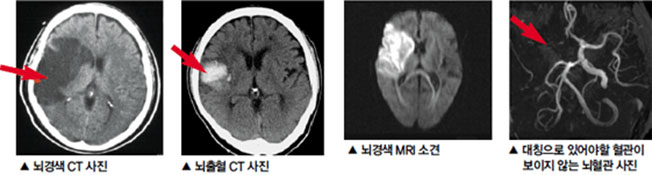

뇌경색은 혈관이 좁아지거나 막히면서 발생하는 뇌의 손상입니다. 이는 주로 혈전이나 색전으로 인해 발생하며, 그로 인해 뇌의 특정 부분에 oxygen과 영양소가 공급되지 않게 됩니다. 이 상태가 지속되면 뇌세포는 영구적으로 손상을 입거나 죽게 됩니다.

뇌경색에는 두 가지 주요 유형이 있습니다. 첫 번째는 허혈성 뇌경색으로, 대개 혈전이 혈관을 막아 발생합니다. 두 번째는 출혈성 뇌경색으로, 뇌혈관이 파열되거나 약해져 출혈이 발생하는 것입니다. 본 포스팅에서는 주로 허혈성 뇌경색의 초기 증상에 대해 설명드리겠습니다.